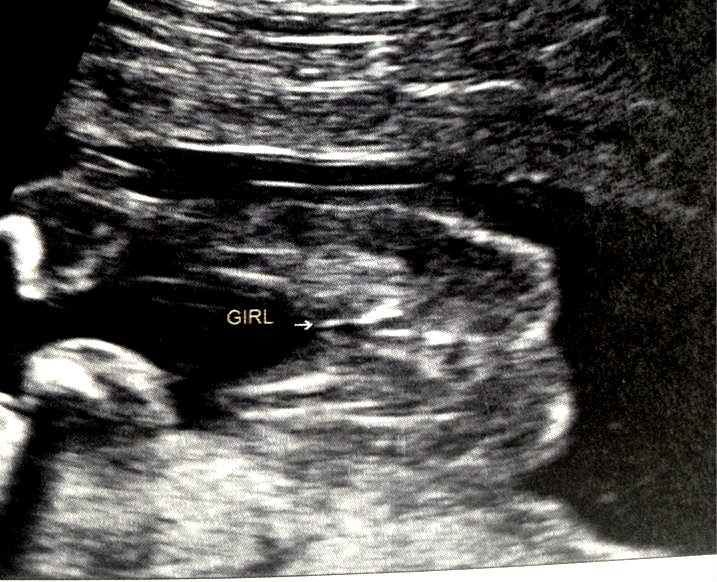

Can u please confirm Attachment 7811